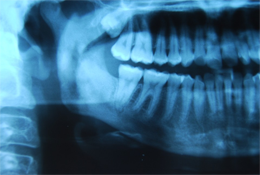

Six mois après la procédure initiale, la patiente a passé une imagerie plus poussée visant à évaluer une cavité médullaire dense de l'os dans la mandibule droite, mise en évidence sur une radiographie panoramique (ill. 1). La tomodensitométrie et la résonance magnétique ont confirmé la présence d'une ostéomyélite diffuse avec atteinte du corps droit du maxillaire inférieur (ill. 2). Aucun séquestre n'était visible à la radiographie. À ce stade, l'ouverture interincisive maximale de la patiente avait été réduite à 20 mm. Les analyses sanguines, y compris la formule leucocytaire, ne montraient rien de particulier.

Ill. 1: Radiographie panoramique du processus ostéomyélitique associé au corps, à la branche montante et au condyle du maxillaire inférieur droit.